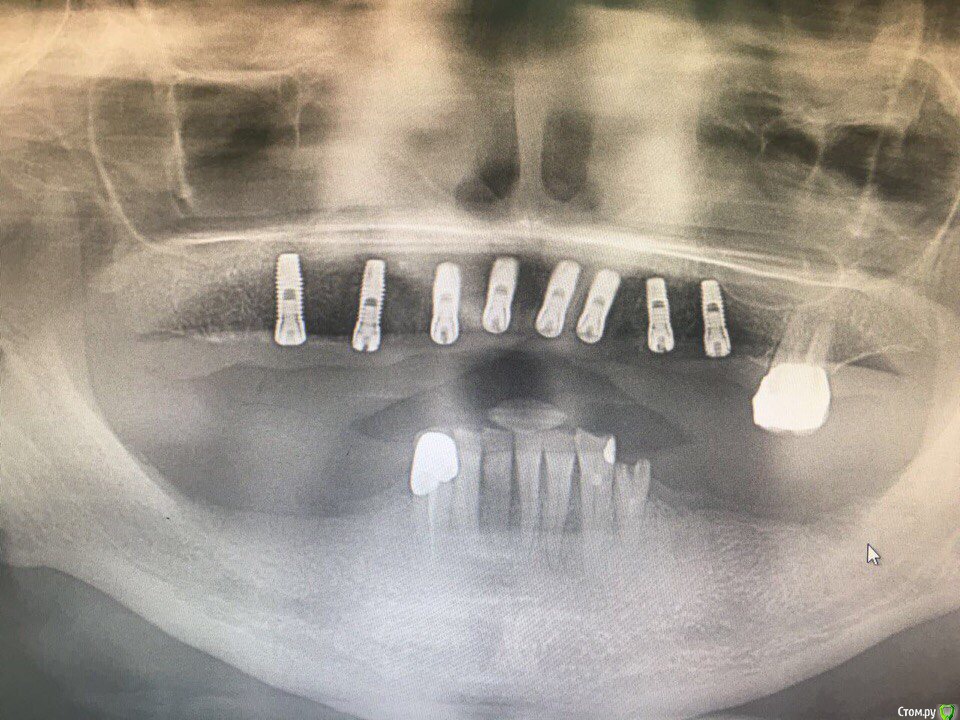

ksenistom Опубликовано 28 мая, 2017 Поделиться Опубликовано 28 мая, 2017 Уважаемые доктора,поделитесь опытом отдаленного протезирования на циркониевой дуге с цементной фиксацией,у меня сейчас сдаётся работа на титановых индивидуальных угловых абатментах,соответственно на них дуга будет фиксироваться. У меня опасения по поводу самой дуги,не будет ли сколов на ней от нагрузки в последствии?И самое страшное,как быть если раскрутится один из винтов в этой конструкции? Ссылка на комментарий

ksenistom Опубликовано 28 мая, 2017 Автор Поделиться Опубликовано 28 мая, 2017 а кто планировал эту работу?и зачем тут делать дугу?Планирования не было,ко мне пациентка попала уже по рекомендации.По другому эстетики не добиться. Мы разрезали дугу попалам. Ссылка на комментарий

ksenistom Опубликовано 28 мая, 2017 Автор Поделиться Опубликовано 28 мая, 2017 всмысле "планирования не было"?это как так?) ну разрезали,и что дальше?зачем тут имплантаты в области центр резцов?и что за система?раз задаете такие вопросы-то получите впоследствии и сколы и раскручивание винтов абатментов,со всеми вытекающимиВ смысле,что ко мне пациент пришла когда у неё уже стояли импланты.Система дентиум. Разрезали с целью устранения баланса на дуге,по другому она не досиживалась.А чем Вам не понравились центр. импл? Ссылка на комментарий

suballex Опубликовано 29 мая, 2017 Поделиться Опубликовано 29 мая, 2017 В смысле,что ко мне пациент пришла когда у неё уже стояли импланты.Система дентиум. Разрезали с целью устранения баланса на дуге,по другому она не досиживалась.А чем Вам не понравились центр. импл?Баланс на ДЦ, это однозначное перепиливание. В смысле - новая фрезеровка. Замыкать верхнюю челюсть жестким материалом - не самая лучшая идея. Правильно боитесь. Выход - первичка из металла, вторичка - ДЦ и одиночки IPS. Или первичка из Тринии + одиночки, они и закроют шахты винтов.Кстати, тут совершенно не нужна подкова.. 1 Ссылка на комментарий